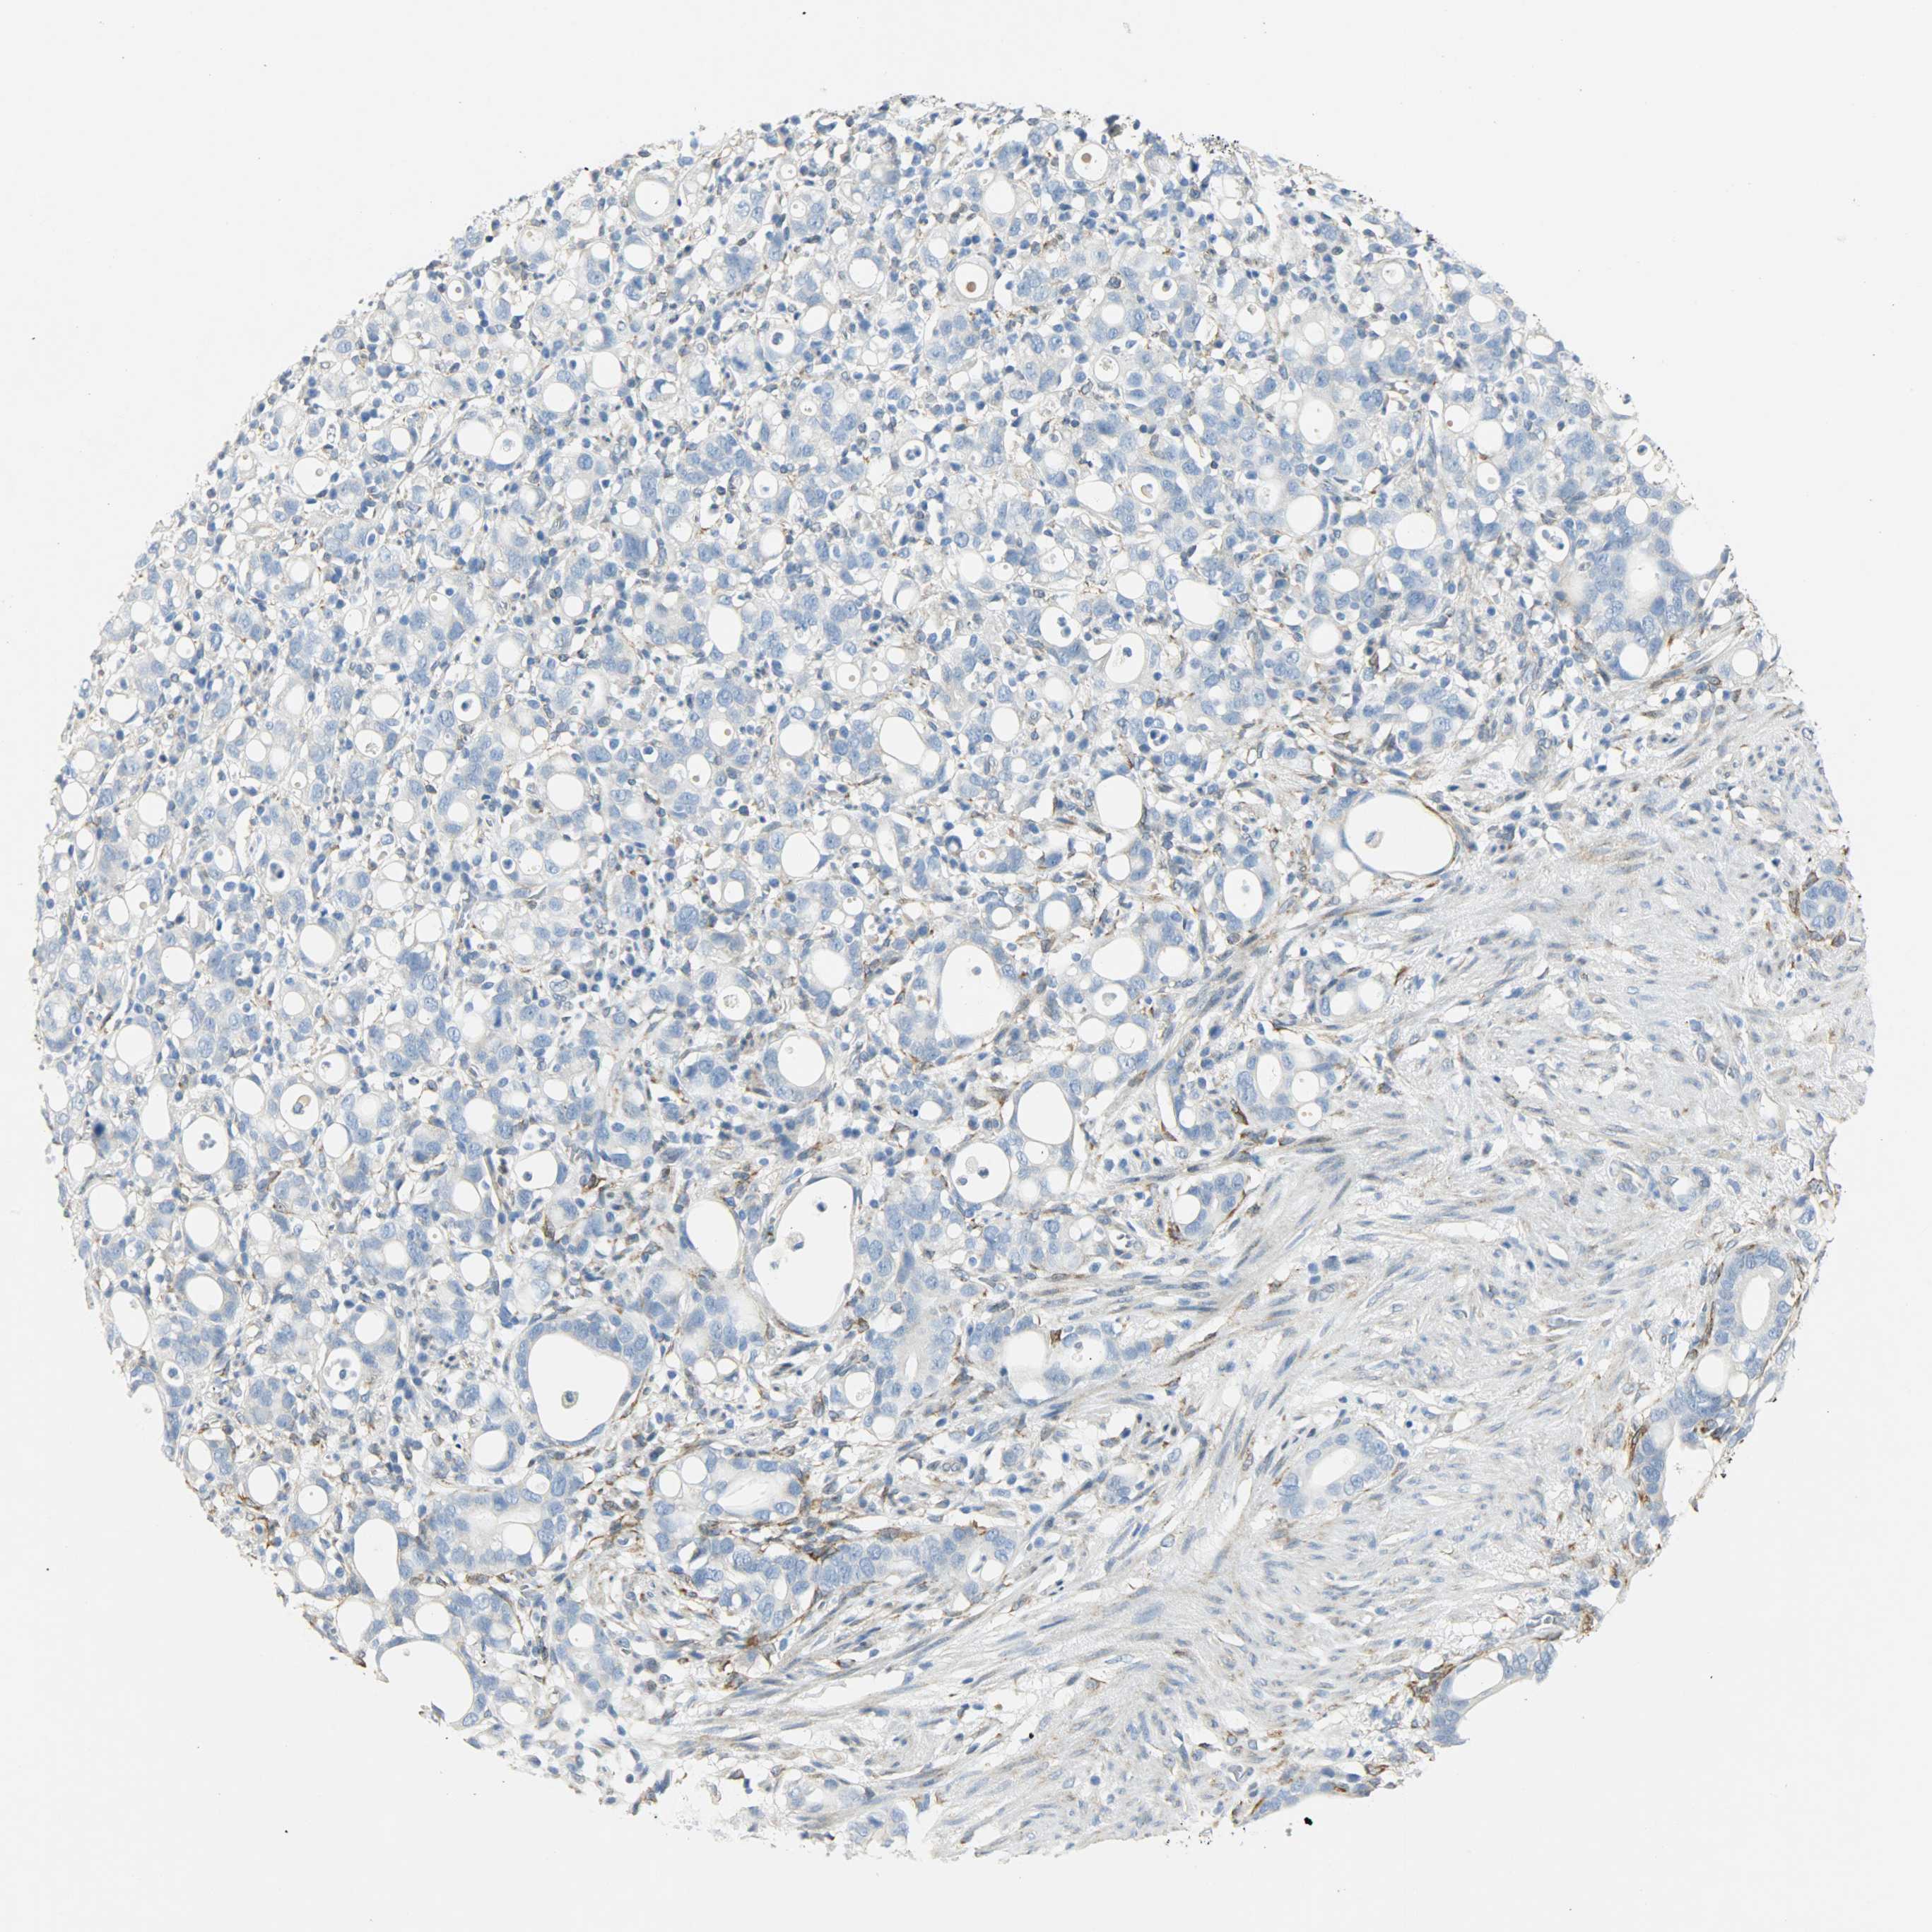

STOMACH CANCER - Protein expressioni

A mouse-over function shows sample information and annotation data. Click on an image to view it in a full screen mode. Samples can be filtered based on level of antibody staining by selecting one or several of the following categories: high, medium, low and not detected. The assay and annotation is described here.

Note that samples used for immunohistochemistry by the Human Protein Atlas do not correspond to samples in the TCGA dataset.

Antibody stainingi

Antibody staining in the annotated cell types in the current human tissue is reported as not detected, low, medium, or high, based on conventional immunohistochemistry profiling in selected tissues. This score is based on the combination of the staining intensity and fraction of stained cells.

Each image is clickable and will lead to virtual microscopy that enables deeper exploration of all samples and also displays staining intensity scores, fraction scores and subcellular localization as well as patient and tissue information for each sample.

Antibody HPA015794

Antibody CAB004544

Staining

High

Medium

Low

Not detected

Intensity

Strong

Moderate

Weak

Negative

Quantity

>75%

75%-25%

<25%

None

Location

Nuclear

Cytoplasmic/membranous

Cytoplasmic/membranous,nuclear

Adenocarcinoma, NOS

Adenocarcinoma, High grade